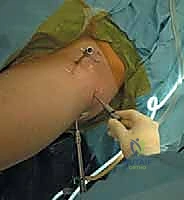

يتم إجراء العملية في بيئة معقمة تماماً ومجهزة بأحدث التقنيات العالمية. إليك الخطوات التي يتبعها فريق الدكتور هطيف:

يتم غالباً استخدام التخدير العام أو النصفي. يوضع المريض على طاولة عمليات خاصة تُسمى (Traction Table). يتم سحب الساق برفق شديد لفتح مسافة صغيرة جداً في مفصل الورك (حوالي 1 سم) تسمح بإدخال الكاميرا والأدوات الجراحية بأمان دون إتلاف الغضروف.

2. إحداث الشقوق وإدخال الكاميرا

يتم عمل شقين أو ثلاثة شقوق صغيرة. يُضخ سائل معقم داخل المفصل لتوسيعه وغسل أي بقايا، ثم يتم إدخال كاميرا الألياف الضوئية (Arthroscopy) التي تنقل صورة مكبرة وعالية الدقة (4K) إلى شاشات العرض.

3. تقييم الضرر والإصلاح

بناءً على التشخيص المسبق والرؤية المباشرة، يبدأ الجراح في العمل:

* إذا كان هناك تمزق في الشفا، يتم استخدام أجهزة خياطة دقيقة لتثبيته.

* إذا كان هناك اصطدام عظمي (FAI)، يتم استخدام جهاز حفر ميكروسكوبي (Shaver/Burr) لنحت العظم الزائد وإعادة تشكيله.

4. الإغلاق

بعد التأكد من إصلاح كافة المشاكل واستعادة الحركة الحرة للمفصل، يتم إخراج الأدوات، وتفريغ السائل، وإغلاق الشقوق الصغيرة بغرز تجميلية بسيطة ووضع ضمادات معقمة.